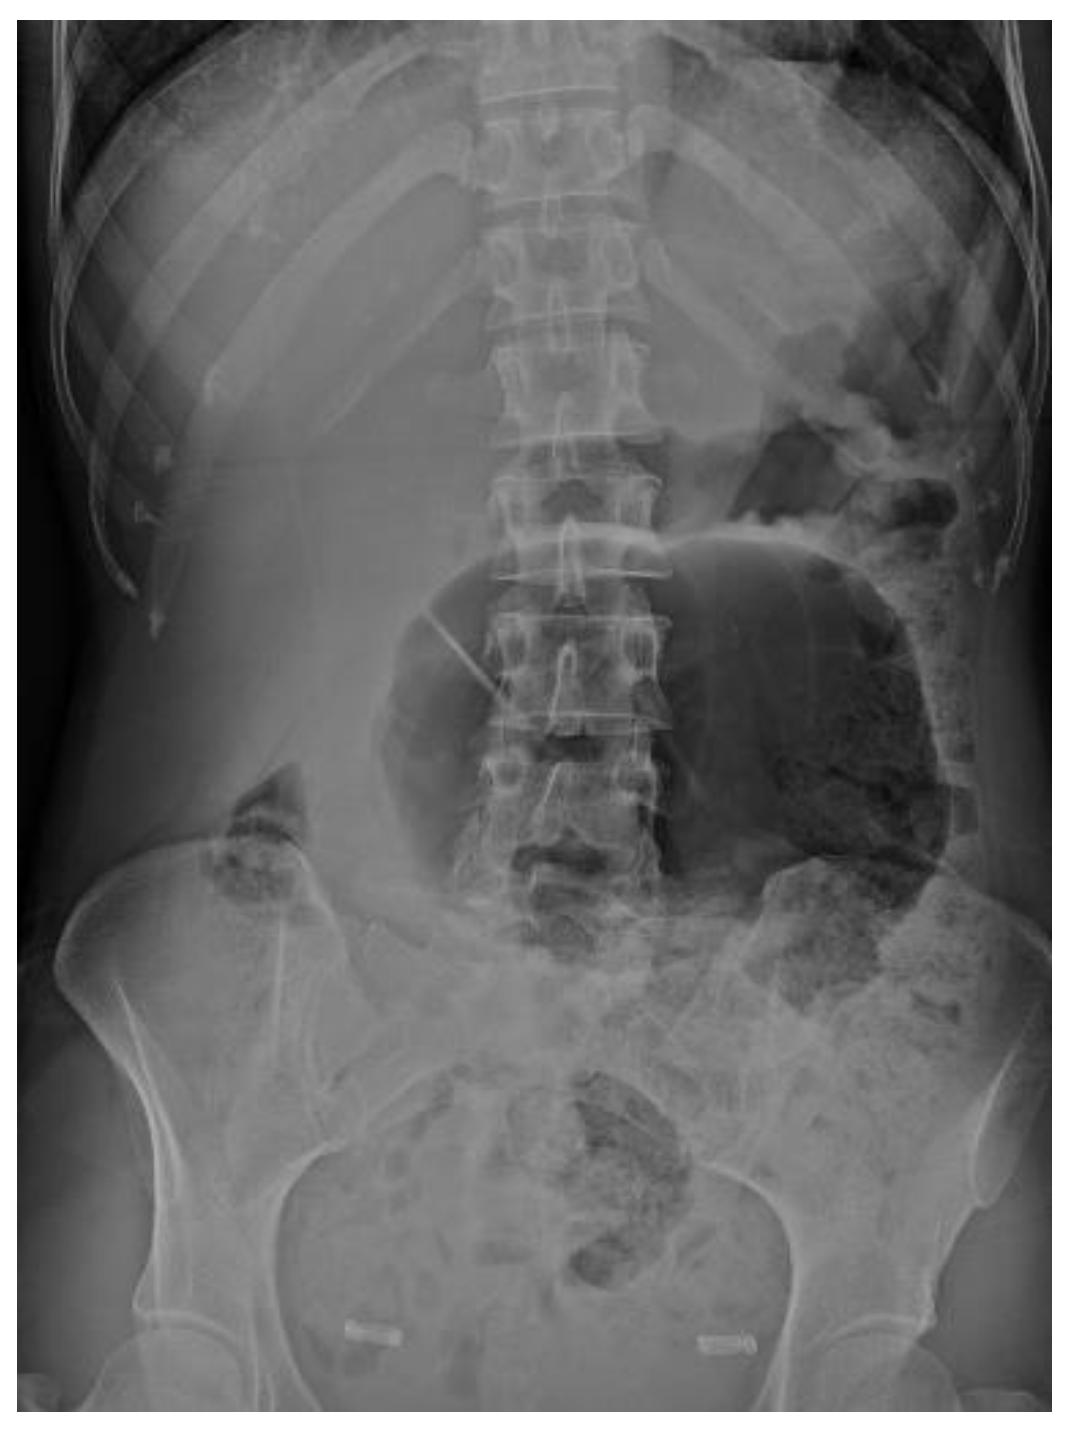

4.4.1. Conventional Radiography

| Abdominal radiograph | 11 (68.75%) | Five patients had CT as the only imaging. |

| Non-specific bowel loops/SBO | 5 (46%) | |

| Classical single loop of large bowel | 6 (54%) | |